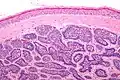

| Dermal cylindroma treated with X-rays without recurrence |

Dermal cylindromas are:

- Dermal lesions consisting of nests of cells that are surrounded by hyaline (i.e., glassy, eosinophilic, acellular) material and have:

- Hyperchromatic nuclei that may palisade (columnar nuclei arranged around the periphery of the cell nests with their short axis tangential to the nest periphery), and

- Cells with lighter staining ovoid nuclei at their centre.

They lack of a significant number of lymphocytes; this differentiates them from spiradenomas.